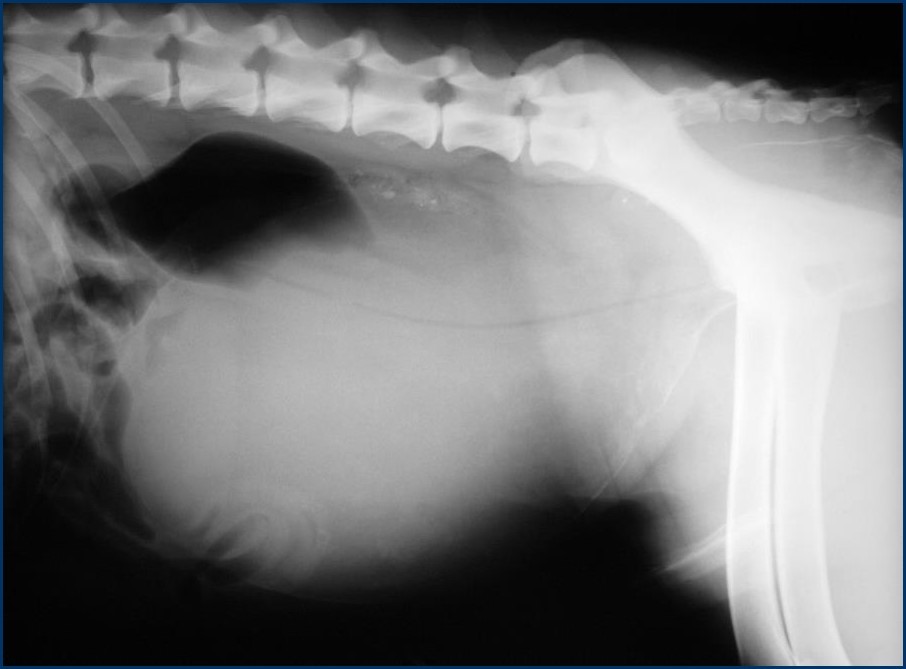

Hamatouria, dysuria

What can be seen?

2 ST opacity – maybe bladder and prostate

What has created this image?

What is seen?

What is the likely diagnosis?

Positive cystogram

Normal cranial bladder

Caudally – bisected structure

Size over 70% of pelvic inlet – prostate

This is classic for BPH – benign prostatic hyperplasia (smooth)